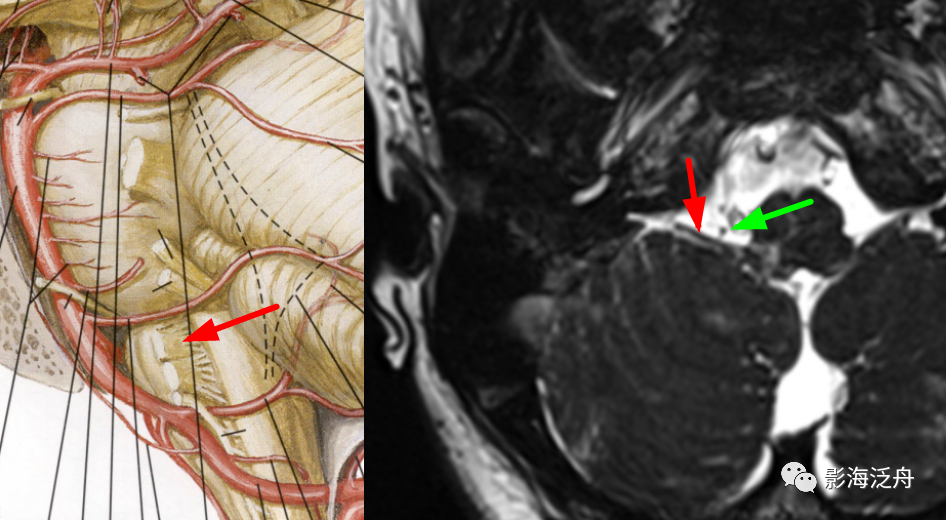

在轴位MR图像上观察并准确辨识出相应的神经和血管,常规的FSE T2WI也可以看到这些颅神经和血管,但不够清晰,尽量还是在更专业的3D重T2WI序列或3D B_FFE序列上观察,如下图↓

MR是目前诊断面肌痉挛及三叉神经痛的主要检查手段。

T2-TSE3D-RST-TRA成像是重T2成像,脑脊液呈高信号,三叉神经,面听神经和血管在脑脊液的高信号衬托下呈低信号可清晰显示,即使周围很小的血管分支也可能成像。

此外,T2-TSE3D-RST-TRA能对静脉以低信号成像,而且无须造影剂,通过多层面分析可确定压迫血管的来源,与常规磁共振技术相比不仅扫描速度成倍提高,并且通过三维薄层技术弥补对比度和分辨率的损失,获得高分辨率、高信噪比的图像,是检查脑神经和血管成像的最佳技术。